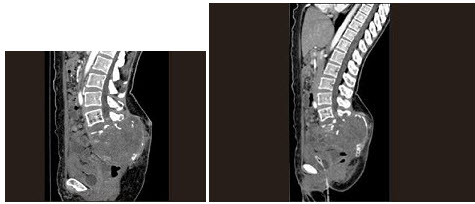

B.脑星形细胞瘤

女,64岁,左侧腰部胀痛,行CT扫描,如图所示,下列说法正确的是()

A.左肾区可见一巨大的占位性病灶,境界较清楚,胰腺尾部受压向前推移

B.该病灶密度不均匀,其内可见脂肪密度影,且呈不均匀强化

C.考虑为左肾来源的血管平滑肌脂肪瘤

D.考虑为左侧肾上腺来源的髓样脂肪瘤

E.考虑为腹膜后来源的脂肪肉瘤